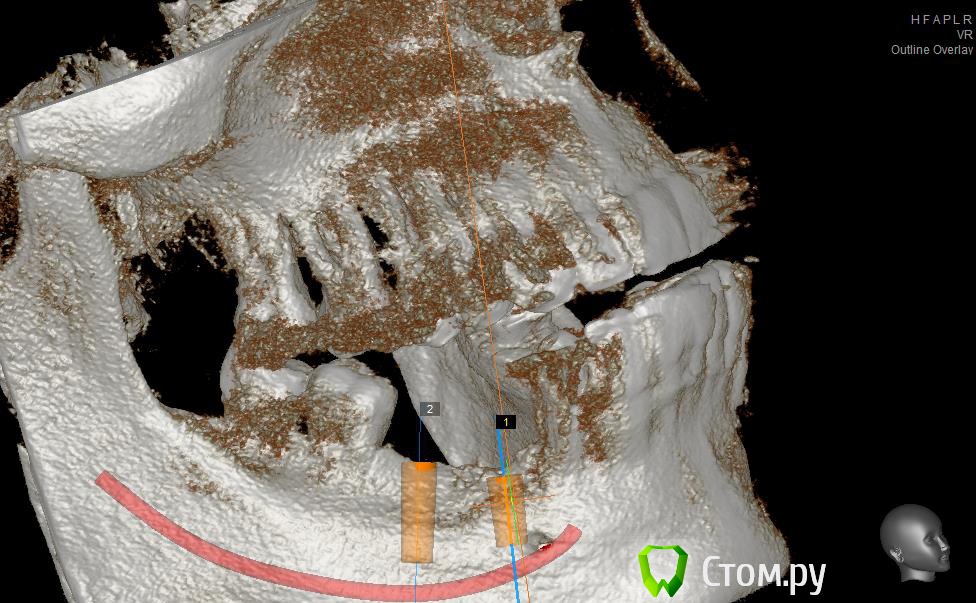

Neilrus Опубликовано 2 марта, 2014 Поделиться Опубликовано 2 марта, 2014 (изменено) Здравствуйте, коллеги, уделите 6 минут новичку…у меня тут проблема, она абсолютно не проблема для того, кто хоть пару раз делал расщепление гребня,а я вот только курсы закончил и у меня планируется через 7 дней операция. Вроде все понял, но пока стремаюсь.Посморите снимки, пожалуйста, а я напишу тот протокол, который хочу применить, как на курсах понял, поправьте, если что не так )) Спросил бы у лектора, но ведь так всегда, да?)Планирую иплантаты по месту 45,46 зубов.Гребень узкий в обл 45 з и близко нч нерв, как раз поднимается к ментальному отвертстию. С этим и связан страх. Никаких транспозиций делать пока не готов. В арсенале нет пьезотома пока, вот пару таких операций сделаю и куплю.Планирую поставить 4,2*8 для 45 зуба и 4,2*11,5 для 46 зуба (Мis Seven) . Соединю коронки, т.к. премоляр коротковат. Итак, план по захвату таков:1)Разрез чуть язычнее середины гребня, откидываем слиз-надк лоскут с аккуратностью в области менталиса.2)По центру гребня делаем горизонтальный распил сепарационным диском диаметром 7 не доходя до зубов по 3 мм. Глубина распила получается 3,3. Потом беру диск 10 и глубина уже 4,8.3)Мелким 7мм диском делаю дистально вертикальный распил на глубину 3,3 длиной с длину имплантата моляра 11,5, а медиально тем же диском на длину 4-5 мм, ниже страшно, боюсь нерв задеть. На верхушке гребня соединяем распилы (черные линии на моем рисунке). Делаем бором твердосплавным шаром компактостеотомию в преполагаемом месте перелома.4)Берем долото и вставляем в горизонтальный разрез и постукиваниями молоточка продвигаем его на глубину до 8мм по всей длине разреза (длина миниального импланта). Чуть покачивая из стороны в сторону, при этом убирая закругления от диска внутри горизонтального распила. (На рисунке, который сам нарисовал – это красная зона).5)Немного раздвинув края в месте предполагаемых имплантатов пилотом 2мм прохожу на глубину имплантатов. Проверяем параллельность.6)Загоняю по очереди мисовские компрессионные винты на глубину имплантатов до диаметра третьего винта 2,4- 3,7 (т.к. импланты 4,2)7)Теперь они вроде как должны быть нормально раздвинуты ( здесь я не понял, нужно проходить фрезами из хир набора или так хорошо войдут) Может финишной фрезой пройти хотя бы на всю глубину имплантатов? Подскажите, пожалуйста.8)Дальше заполняю пустоты MP3, фиксирую пинами MCT 2.75 мембрану evolution толстую на 2 мм ниже коспактостеотомии, перекидываю на язычную сторону под надкостницу краешек запихиваю.9)Мобилизую лоскут, ушиваю все наглухо и надеюсь на лучшее. ВОПРОСЫ:1)не коротковат ли имплант 4,2*8, но ведь я соединю их? Можно немного наклонить его медиально, выход шахты оставить там же, но апикальную часть ближе к моляру, тогда длина 10 выйдет, но там и так не получается соостно с зубами имплант размстить, а тут его и такая ангуляция, не хорошо, я думаю.2)Отслойка лоскута медиально- правильно я написал или порвется тогда и лучше рассечь связку на 44 и медиально вниз.3)Фрезы хирургические нужно использовать при нормальном раздвигании краев гребня? Кстати, нормально-это сколько для диаметра имплантата 4,24)Язычно нужно как-то дополнительно фиксировать мембрану?5)MP3 мешать с аутокостью и кровью из ловушки?6)Как лоскут мобилизовать медиально рядом с ментальным нервом? Пластика зкпд будет одновременно с открытием.Спасибо вам за ваше время ) Изменено 8 мая, 2014 пользователем Bier Ссылка на комментарий